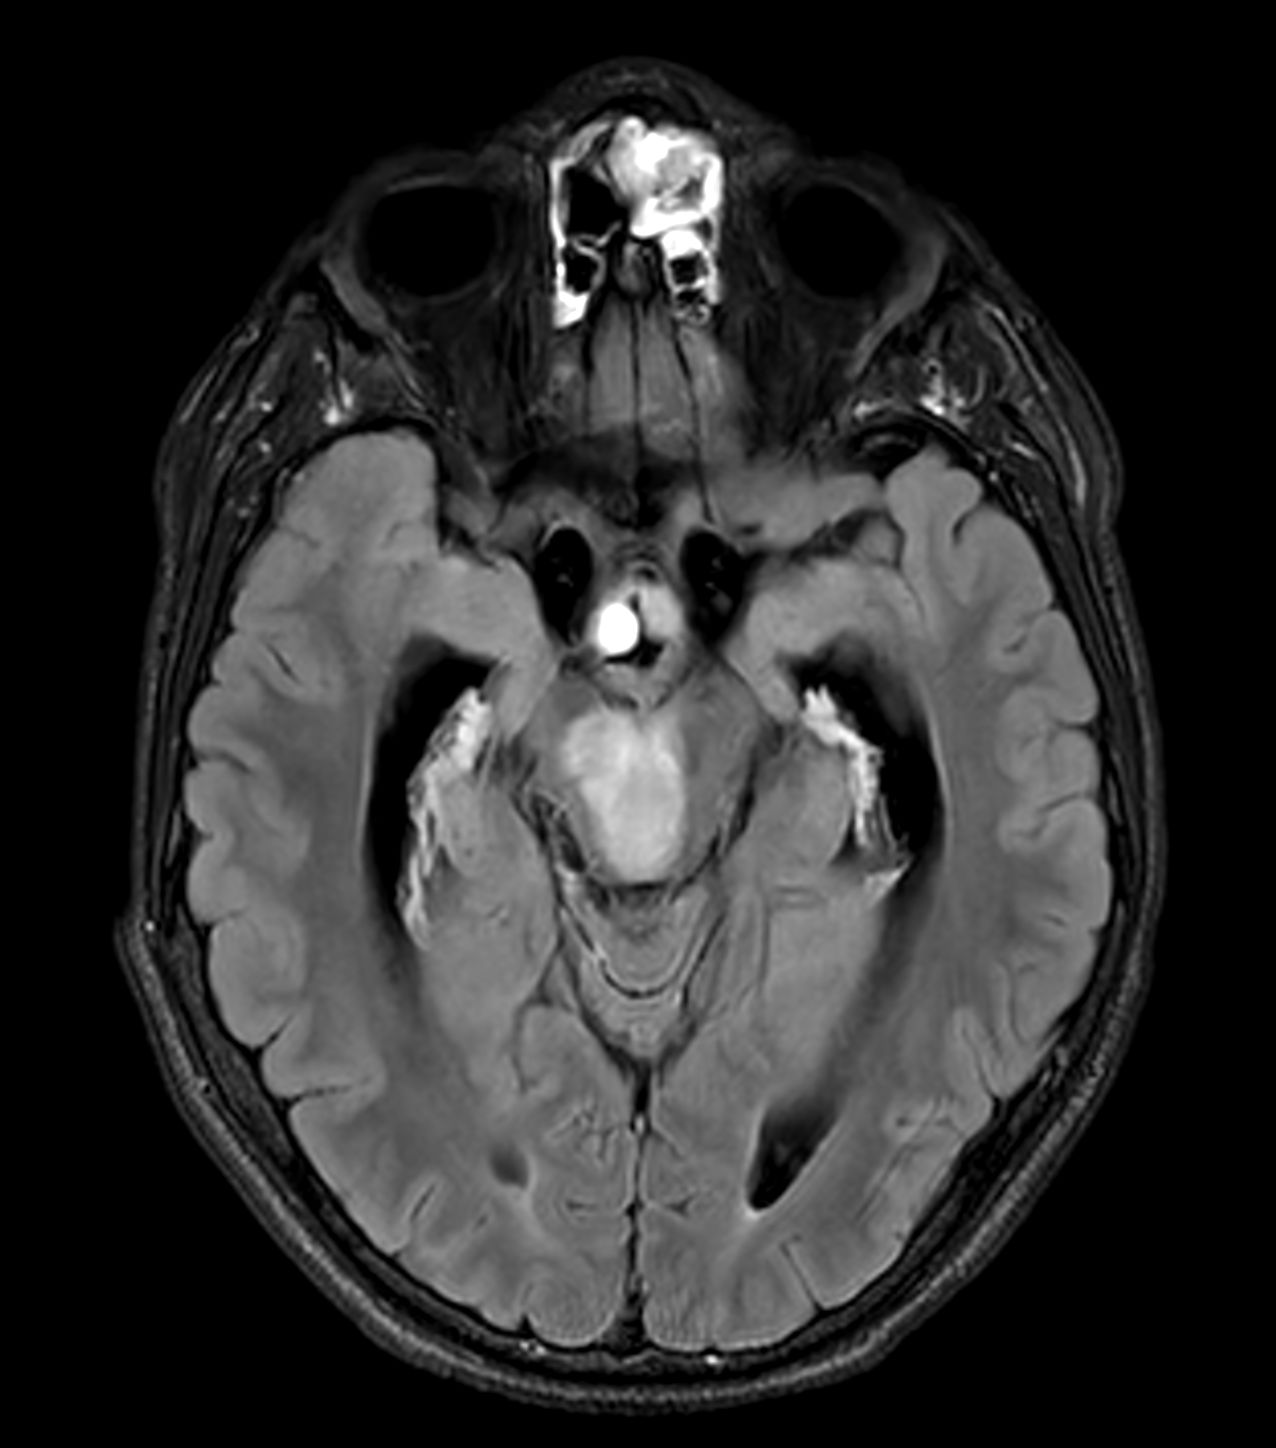

Follow up study of a 12 year old boy with a known low grade glioma.

Axial T2w FLAIR